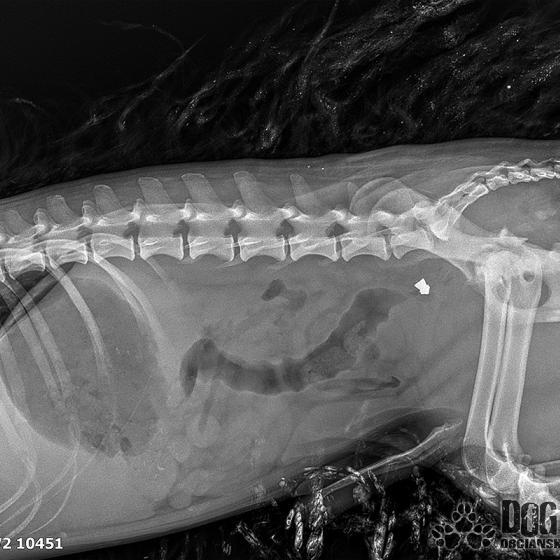

Vianoce nám klopú na dvere a mali by to byť sviatky radosti a pokoja. No u nás nebudú a pre malého Jamesa už vôbec nie. Malého Jamesa sme prijali s mnohonásobnými fraktúrami panvy. Presnejšie, s obojstrannou iliosakrálnou luxáciou/fraktúrou, viacnásobnou fraktúrou panvy, vrátane fraktúry kranialneho acetabula obojstranne. Áno, znie to hrozivo a keď si pozriete snímky z RTG, bude to ešte hrozivejšie (ďalšie snímky ešte doplníme).

Čakali ho teda štyri, veľmi náročné ortopedické operácie, takže sa musel trocha posilniť. Do starostlivosti si ho vzala MVDr. Panyi Terzieva a 17.11. mohol absolvovať prvú operáciu. V "prvom kole" krpec zvládal anestézu tak dobre, že sa rovno mohli spojiť dve operácie a tak sa celá ľavá strana dala do poriadku. Zostal samozrejme naďalej hospitalizovaný. Ďalší zákrok sa naplánoval na 20.11. a našťastie opäť všetko prebehlo hladko, a zoperovala sa celá pravá strana(nechceme sa dlho rozpisovať, prikladáme lekársku správu). James bol prepustený 24.11. ako chodiaci pacient a bez problémov ovládal aj vylučovanie! Je to priam zázrak, za ktorý opäť vďačíme MVDr. Vatolíkovi a jeho teamu.